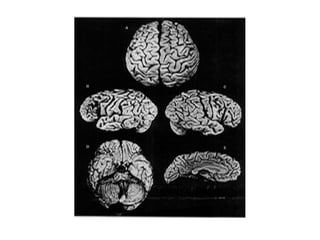

ESTUDIOS EN HUMANOS C.PF. Es la última en madurar La materia gris cae y la blanca aumenta por mielinización =sube conducción y comunicación Aumenta control cognitivo Ganglios basales y C.PF. relacionados con suprimir respuestas inapropiadas y suprimir estímulos irrelevantes

ESTUDIOS EN HUMANOSC.PF. Es la última en madurar La materia gris cae y la blanca aumenta por mielinización =sube conducción y comunicación Aumenta control cognitivo Ganglios basales y C.PF. relacionados con suprimir respuestas inapropiadas y suprimir estímulos irrelevantes